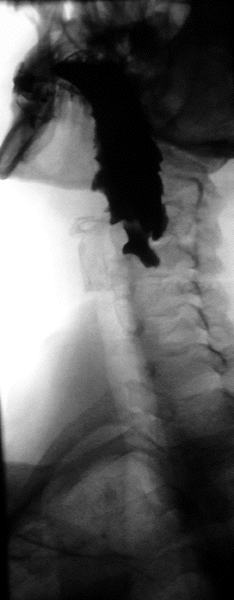

Le diagnostic est radiologique. Aujourd'hui l'imagerie de première intention à effectuer est un scanner cervico-thoraco-abdomino-pelvien avec opacification digestive haute ainsi qu'injection de produit de contraste. Le transit œso-gastro-duodénal historiquement utilisé qui visualise le diverticule sous forme d'une image d'addition du tiers supérieur de l'œsophage n'a pratiquement plus d'indication à l'heure actuelle en raison de la meilleure précision de l'examen TDM[1].